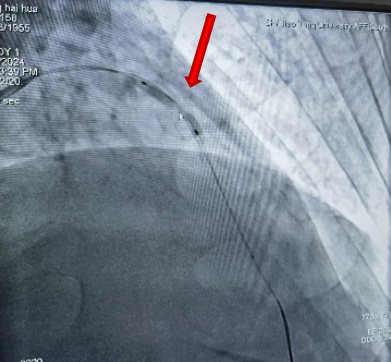

近日,奉贤区中心医院心血管内科开展了奉贤区首例震波球囊术,为复杂冠脉钙化病变再添新武器,进一步开启奉贤区冠脉复杂病变治疗新篇章。 患者张某,69岁,有高血压、糖尿病病史10多年,最近出现不稳定型心绞痛,收住院后择期行冠脉造影检查,造影结果提示:左前降支近段至中远段95%严重狭窄,IVUS(血管内超声)提示360°环形钙化。乔增勇主任团队尝试球囊预扩张,普通球囊+高压球囊反复扩张10余次均不能撼动钙化斑块一丝一毫。乔增勇主任意识到再这样继续扩张下去可能会导致冠脉夹层甚至冠脉穿孔等严重并发症。 高压球囊扩张,呈“狗骨头”效应(箭头处) 在医院的统筹协调下,震波球囊很快到位。乔增勇主任、葛广豪主任医师及杨立国主治医师密切配合,先是利用震波球囊在钙化病变处进行5组脉冲治疗,待钙化的组织被“震碎”后,可见震波球囊完全膨胀,IVUS证实360度“戒指样”钙化环被震开,再次高压球囊扩张后在病变处进行支架植入,术后IVUS进一步证实左前降支架膨胀贴壁好,恢复完全通畅状态,患者病灶得到解除。 术前(前降支95%弥漫性狭窄) 术后狭窄消失 震波球囊技术 震波球囊技术又称血管内冲击波碎石术,是利用设备将电能传递到发射器上,通过发射器产生声波压力波,将球囊内液体汽化,借助气化的液体对血管内膜、中膜的钙化组织进行隔空“敲裂”。 优点: 1.针对性强,只针对钙化组织,对正常血管组织无影响; 2.冲击波治疗后可增加血管顺应性,让血管“恢复年轻态”; 3.有些钙化病变需要震波球囊联合旋磨及切割球囊等“组合拳”方能解决。 奉贤区中心医院心血管内科针对复杂冠脉钙化病变,根据病变特点已成功开展旋磨术,切割球囊及棘突球囊等技术。目前再添新武器“震波球囊技术”,为奉贤区复杂冠脉病变治疗插上新的翅膀,让区内复杂冠脉病变患者不出奉贤即可享受市区三甲医院同质化优质医疗服务。